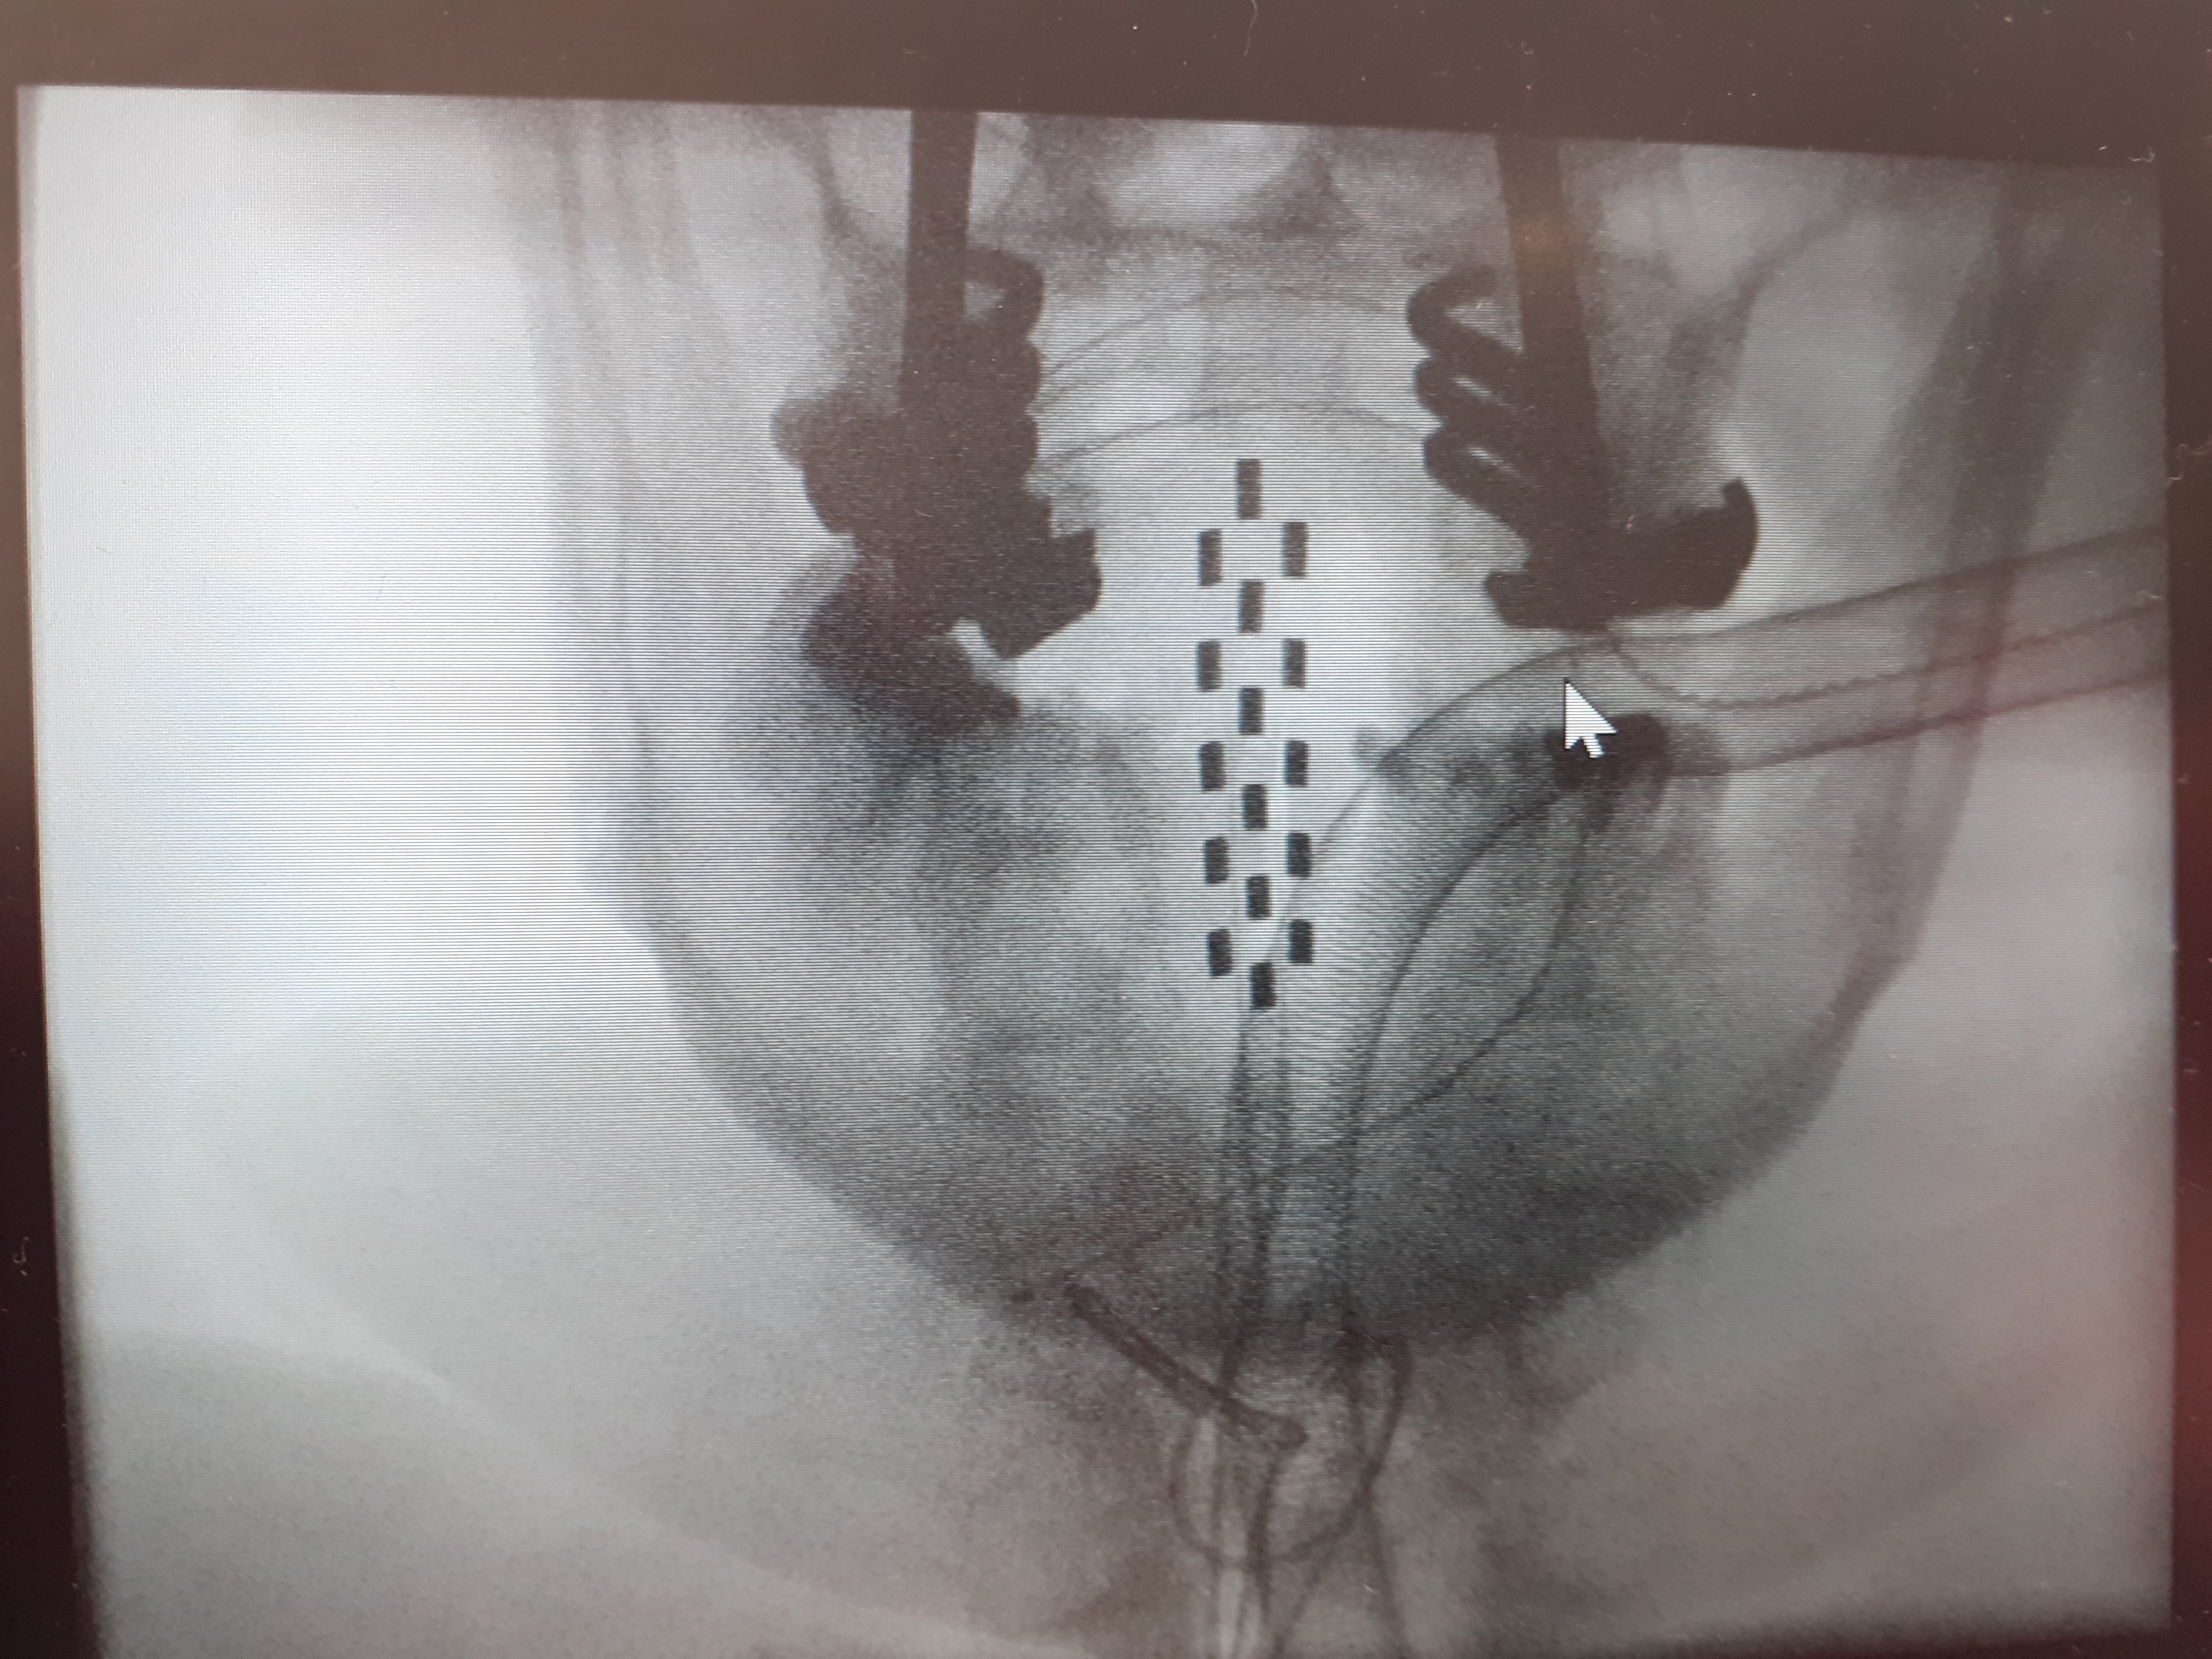

I think I mentioned in my pre-surgery post that I had asked for some pictures of what they were actually doing inside me. I asked again whilst I was at the clinic if the images could be sent over, and I’ve since received them.

The Abbott electrode is not in my mouth as the image suggests, and nor did I have a pair of round glasses on during surgery! Actually, I was unconscious, so who knows if it is a pair of glasses? 😆

The white area next to the electrode in the lateral view is scar tissue that Mr Mundil was worried about removing more than he had because it was extremely hard, and too close to the spinal cord, thus there was risk of damaging the cord. It is unfortunately this scar tissue that is blocking the closed-loop capability as the device needs to receive signals back from the lower end of the paddle to close the loop. They tried sending the input signals to the lower end so that the responses could be picked up from the top where it is close to the cord, but it was not providing any benefit without increasing the power to inappropriate levels.